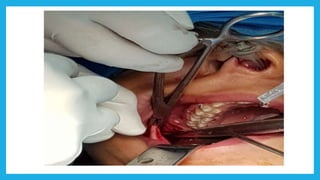

Mandibular orthognathic surgery

It can be divided into several section:-

 Surgery in which the jaw is moved in antrio-posterior

direction by an osteotomy either in the ramus or body of the

mandible

 Surgery to the dentoalveolar area, such as segmental surgery

to shift the teeth and alveolus but maintaining the integrity of

the lower part of the mandible

 Surgery into the chin, moving it in superior , inferior ,

posterior or anterior direction sometimes accompanied by

reshaping